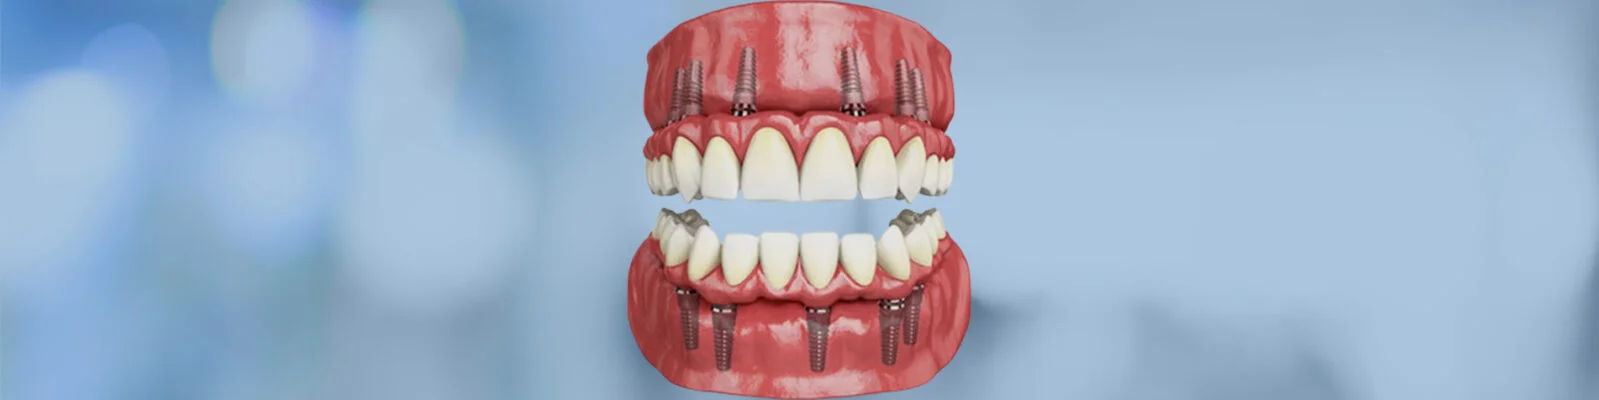

Rebuilding or replacing every tooth in the upper and lower jaws is part of whole mouth rehabilitation, sometimes referred to as full mouth restoration. The use of dental implants in this process has revolutionized the way dentists approach extensive tooth loss or damage. Implants serve as artificial tooth roots made of biocompatible materials like titanium, which integrate with the jawbone, providing a stable and permanent foundation for replacement teeth such as crowns, bridges, or dentures. This procedure does more than just improve appearance; it restores chewing ability, speech, and overall oral health.2. Who Should Consider Full Mouth Rehabilitation?

•Implant Placement: The implants are surgically inserted into the jawbone, usually under local anesthesia.

• Healing Phase: It takes several months for the implants to fuse with the bone, a process called osseointegration.

•Attachment of Prosthetics: After healing, custom-made crowns, bridges, or dentures are fixed onto the implants.